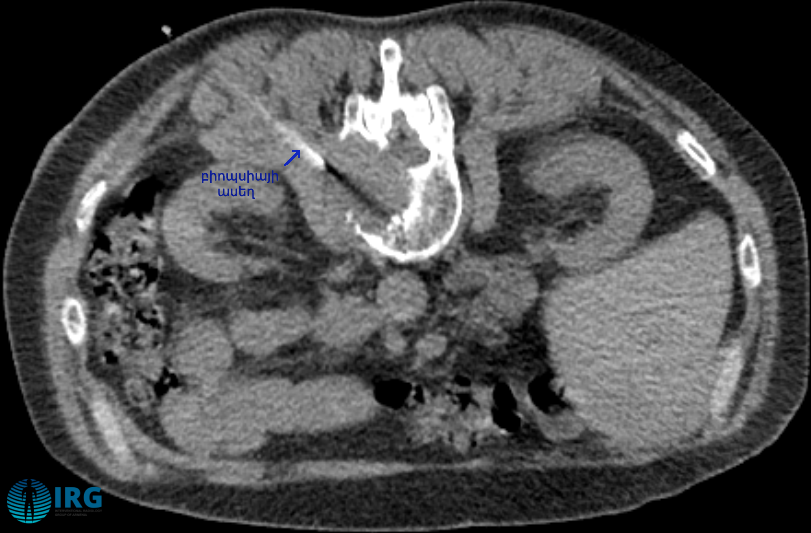

ՀՇ պատկերը միջամտությունից առաջ